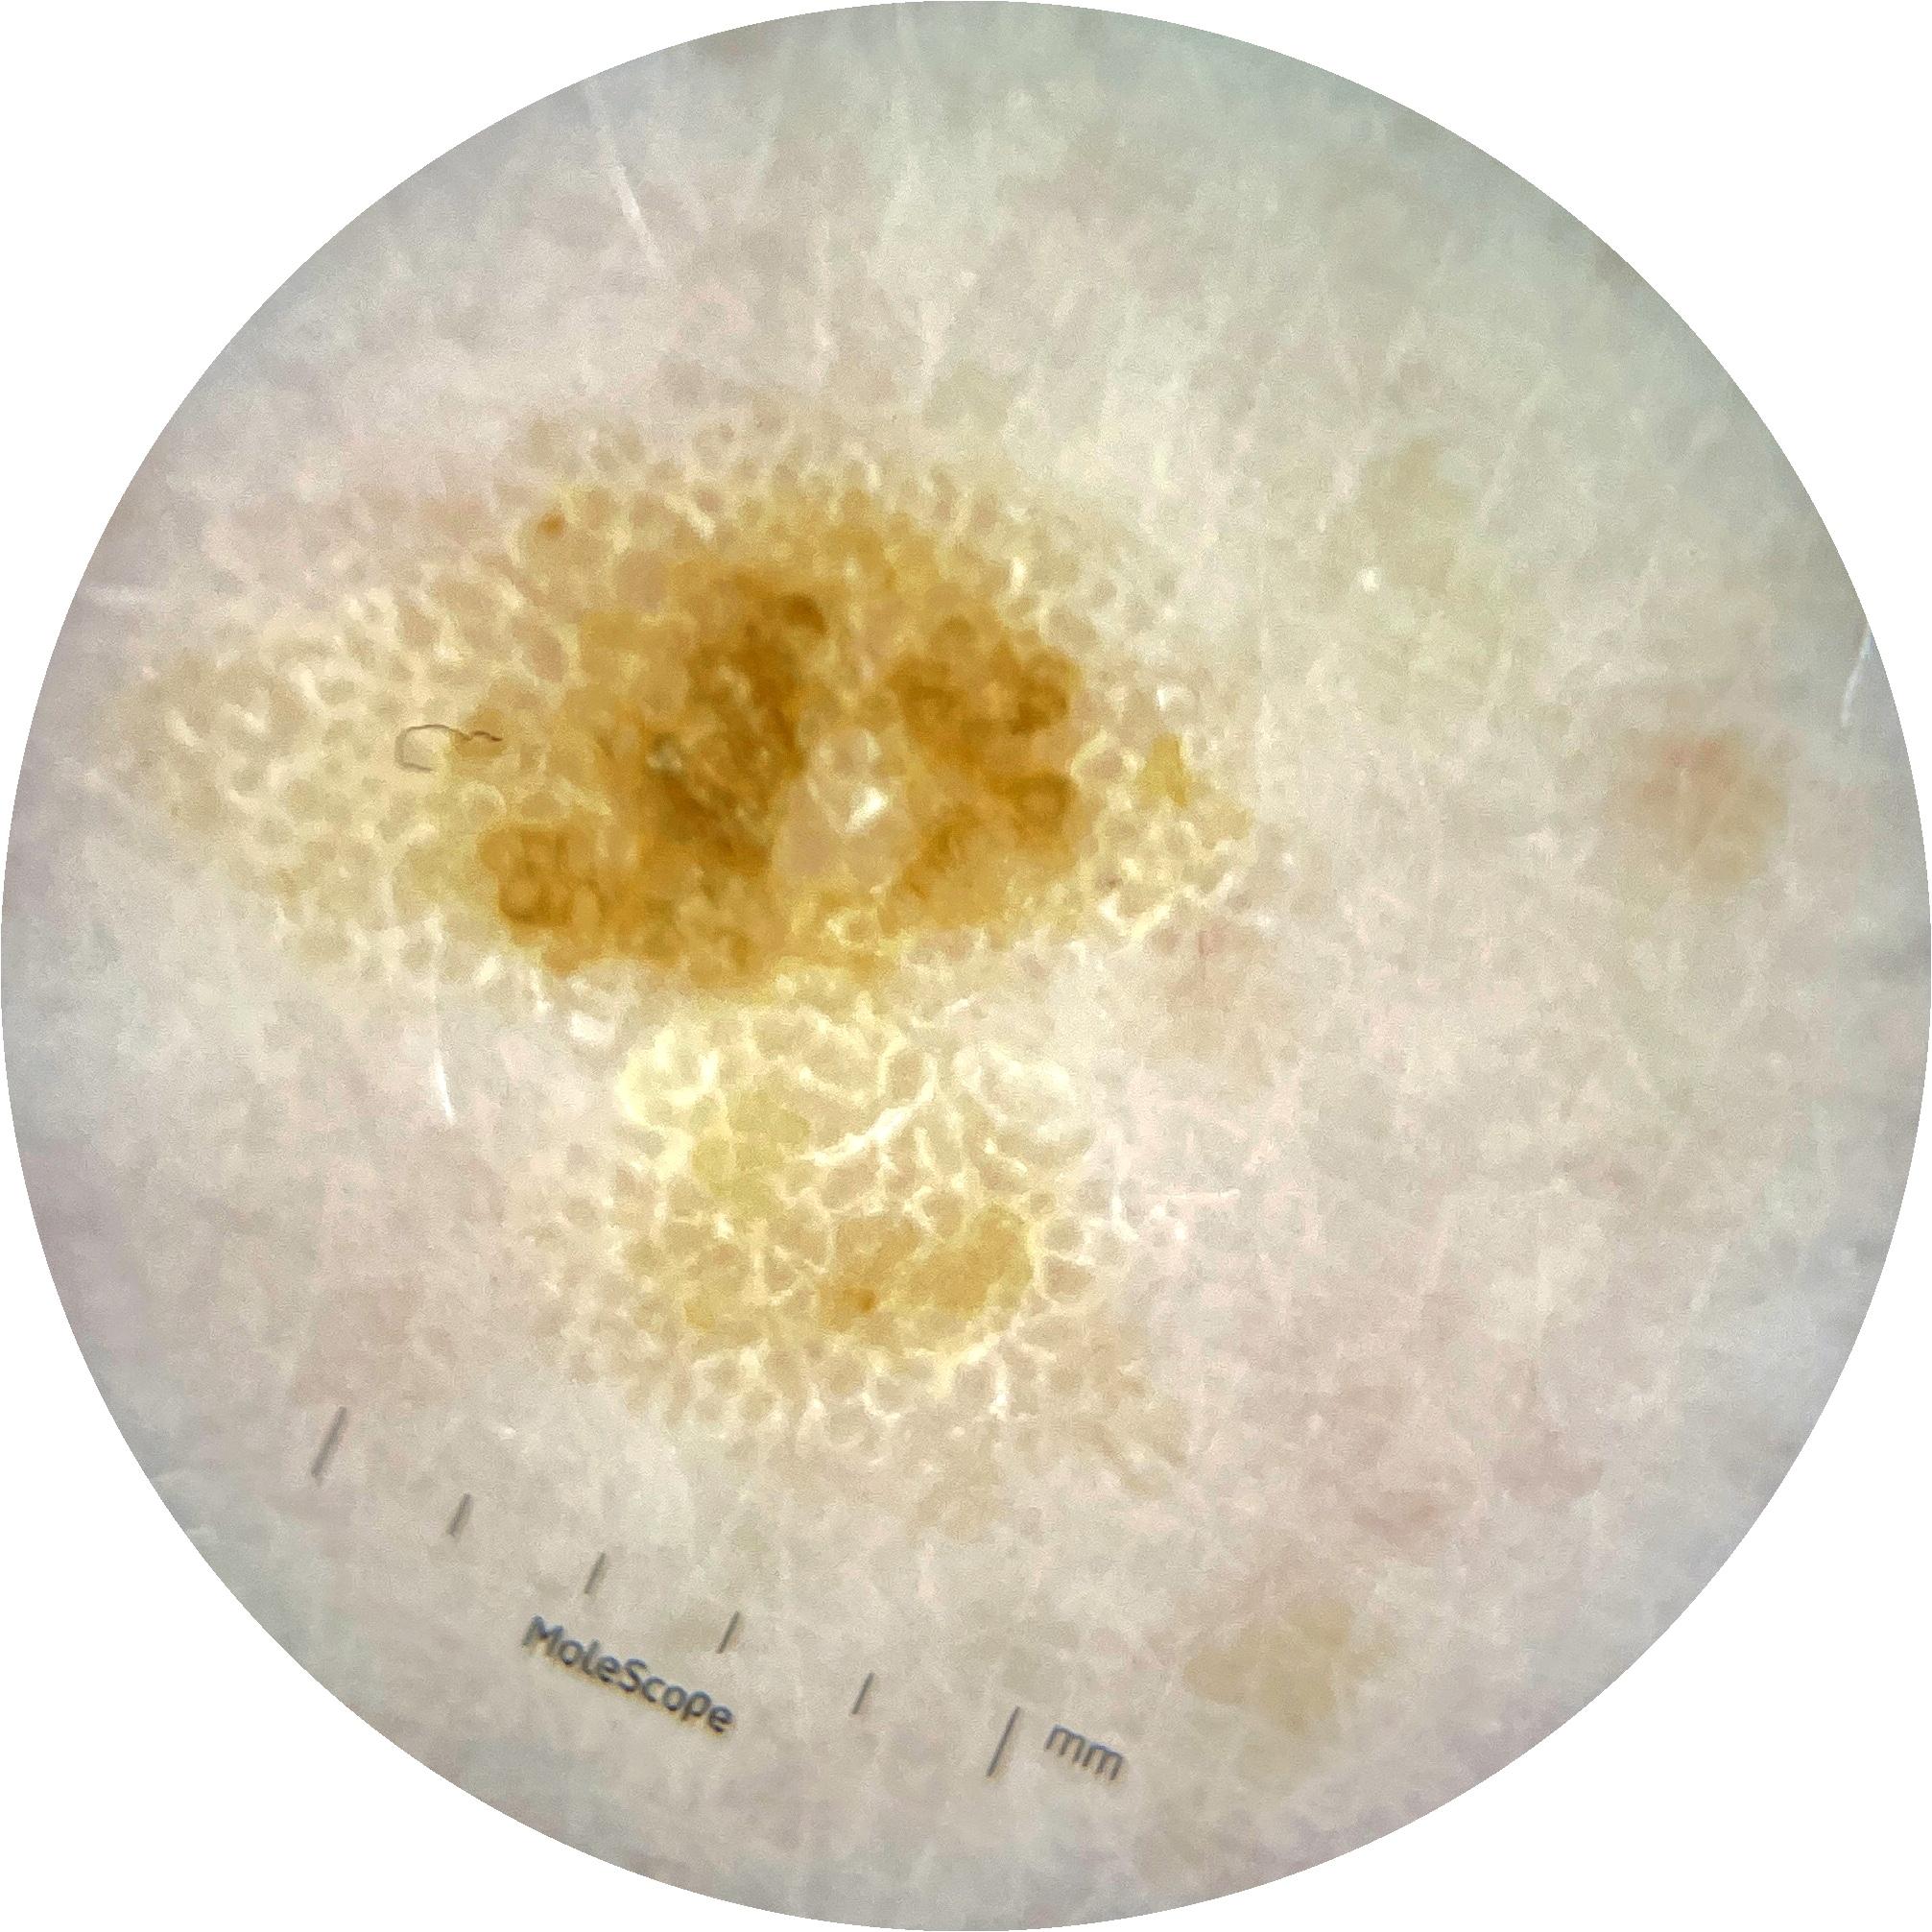

ISIC_9785574

Information

2003 x 2003

Attribute to

MEL-SELF Trial, https://www.sydney.edu.au/medicine-health/our-research/research-centres/melself-project.html

Field Value

acquisition_day 148

age_approx 45

anatom_site_1 Head and neck

anatom_site_general head/neck

concomitant_biopsy False

diagnosis_1 Benign

diagnosis_confirm_type single image expert consensus

family_hx_mm True

image_manipulation instrument only

image_type dermoscopic

lesion_id IL_0236417

patient_id IP_8456088

personal_hx_mm True

sex female